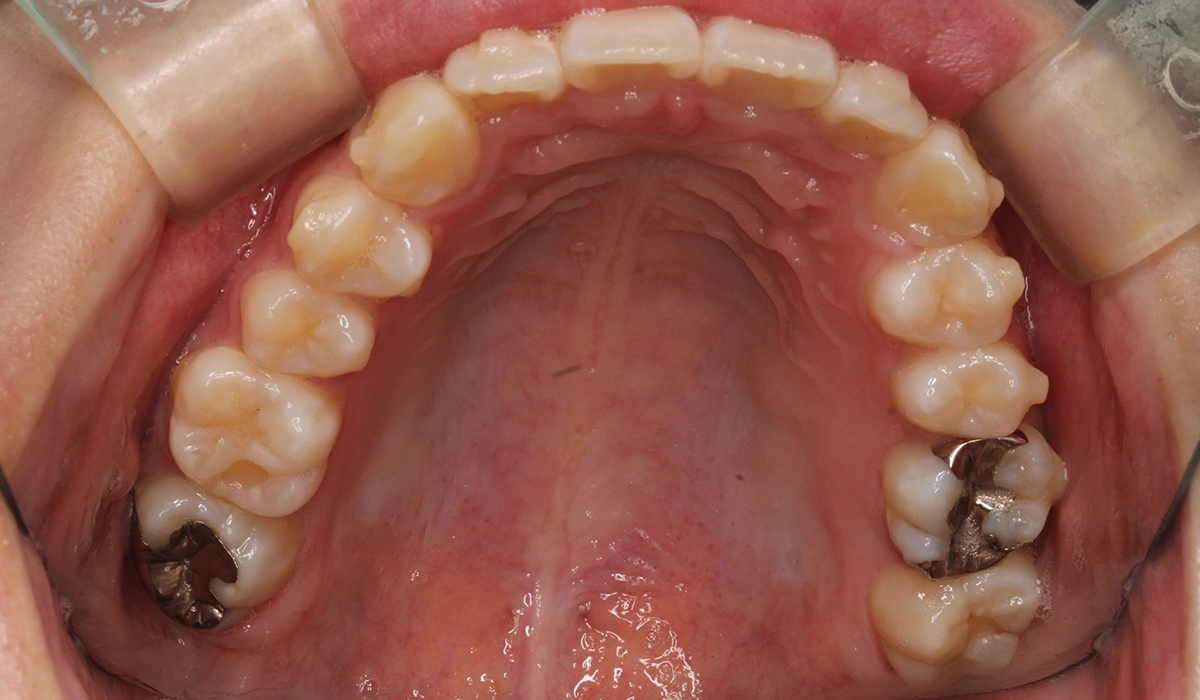

術前:下顎

術後:下顎